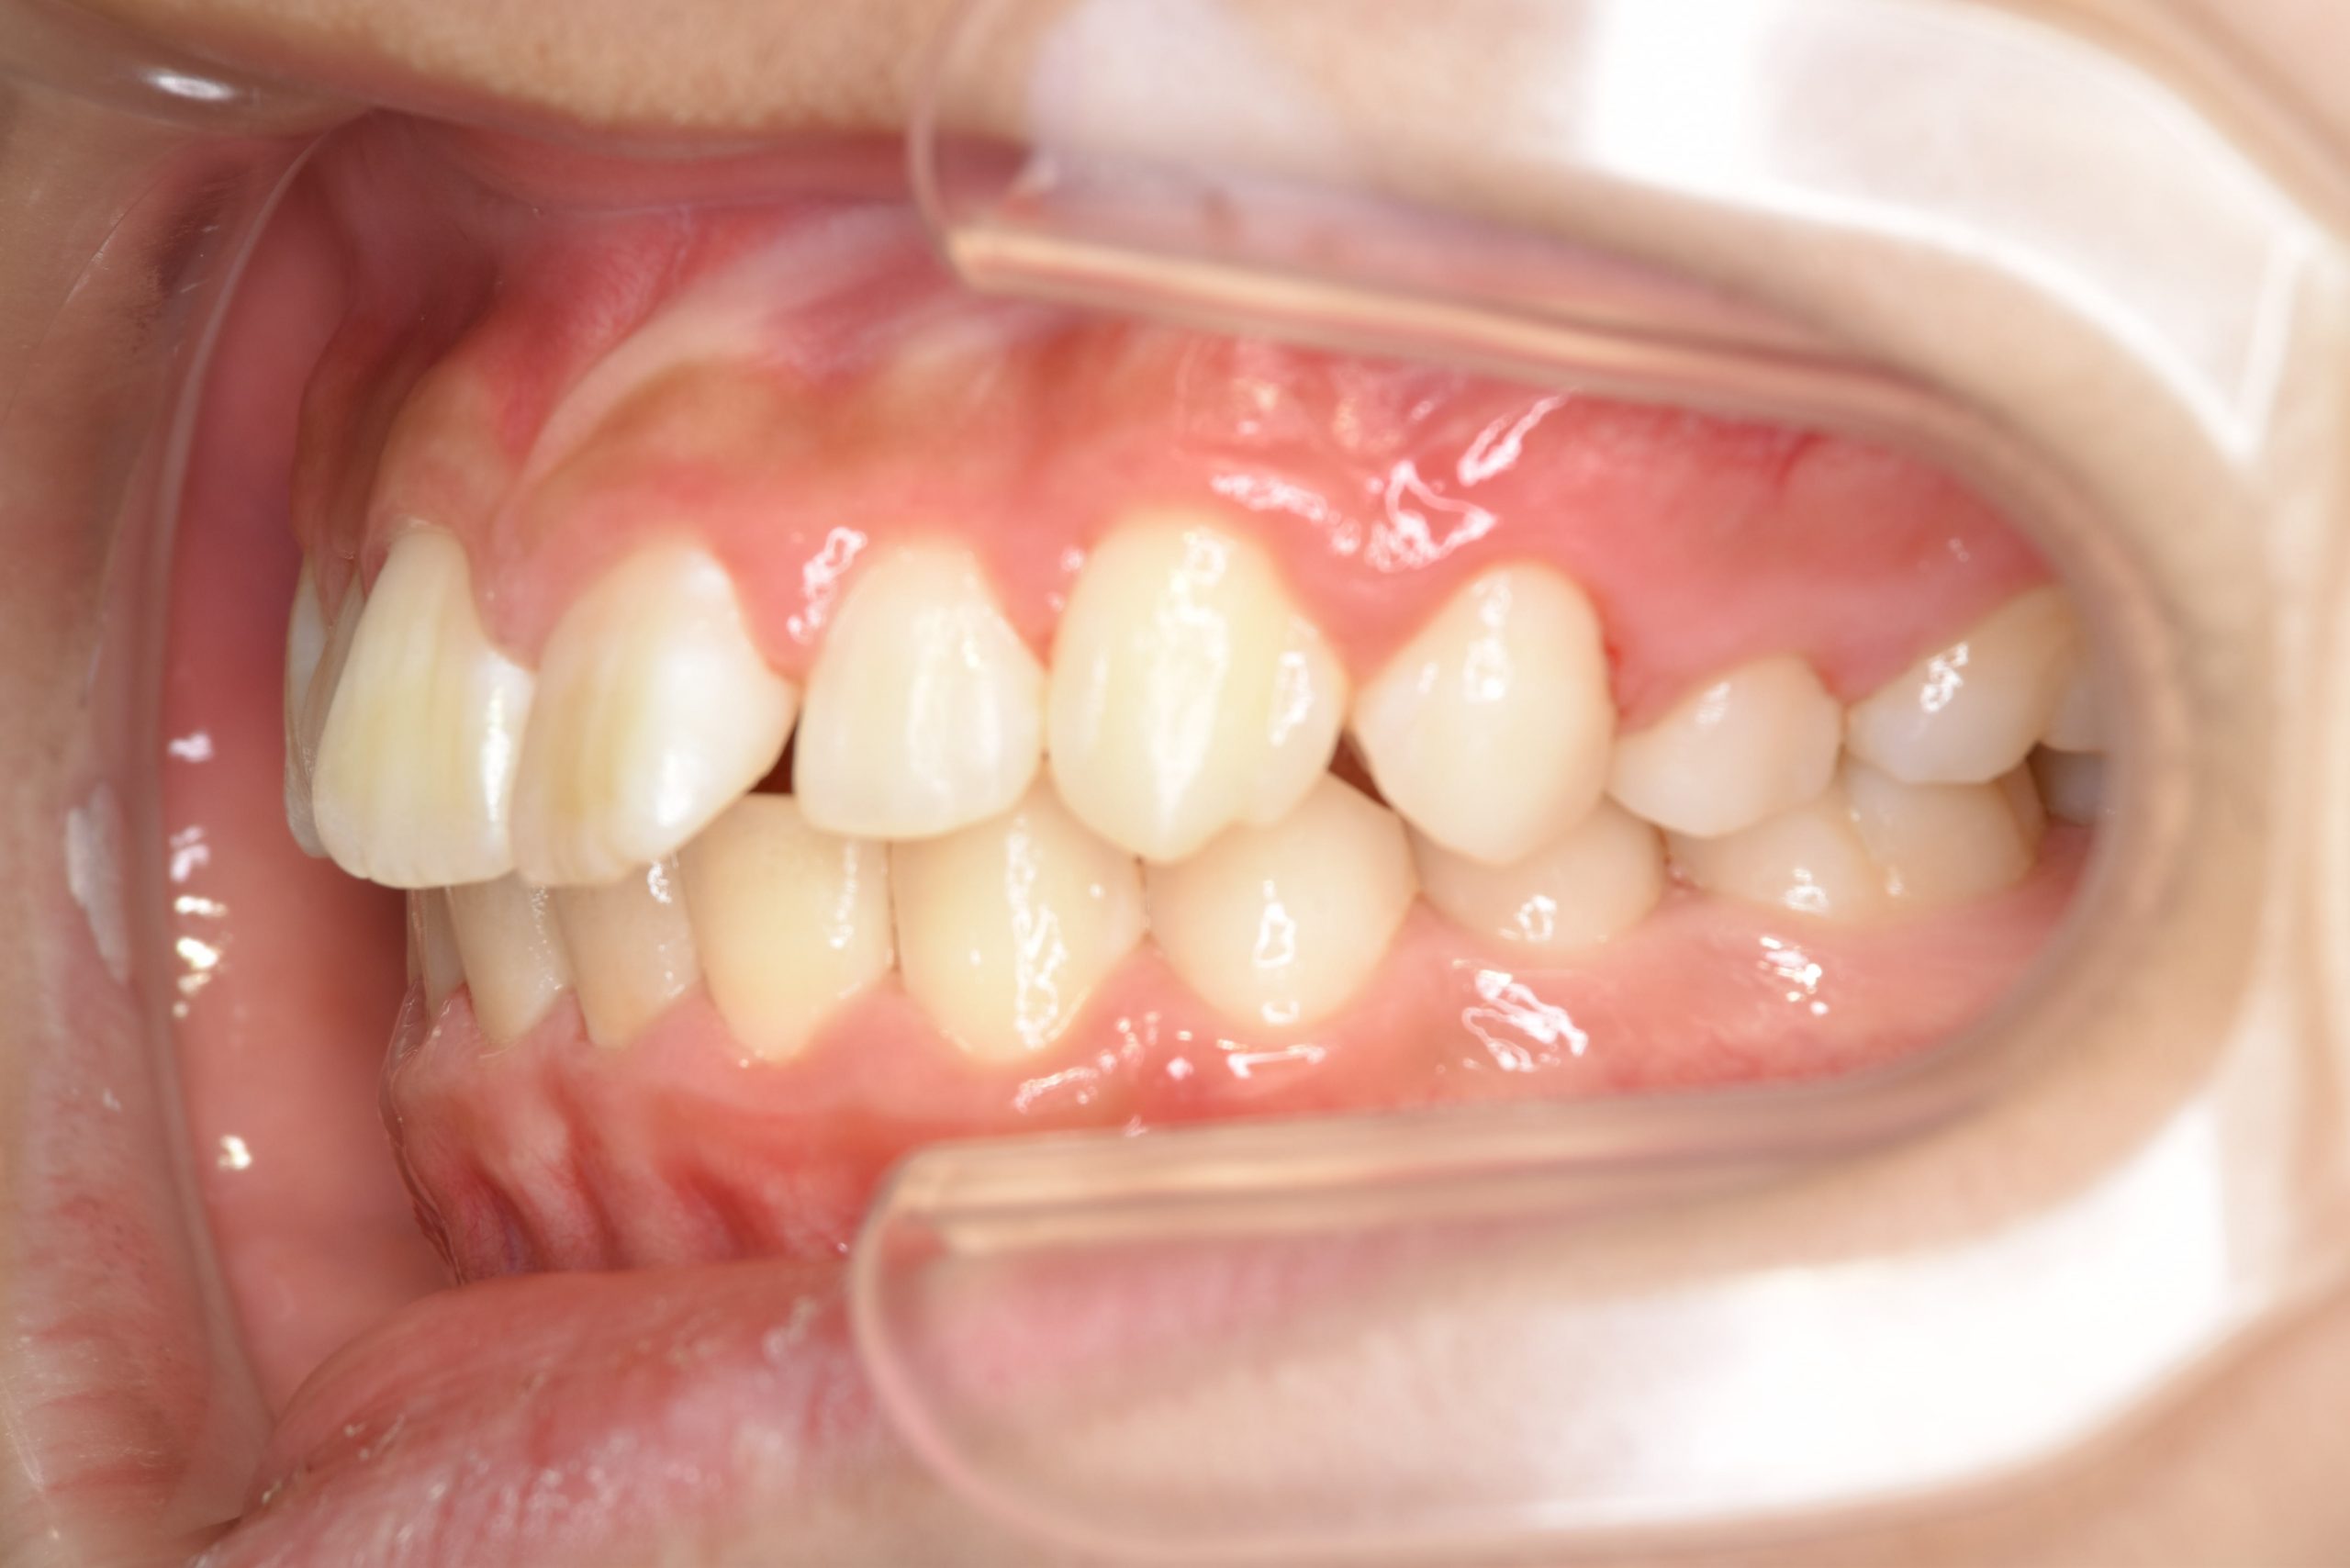

ビフォー

全顎ワイヤー矯正 症例_218

アフター

主訴 出っ歯|歯の隙間

施術内容 小児矯正1期治療

治癒期間 1年11ヶ月間

費用 465,400円(税込)